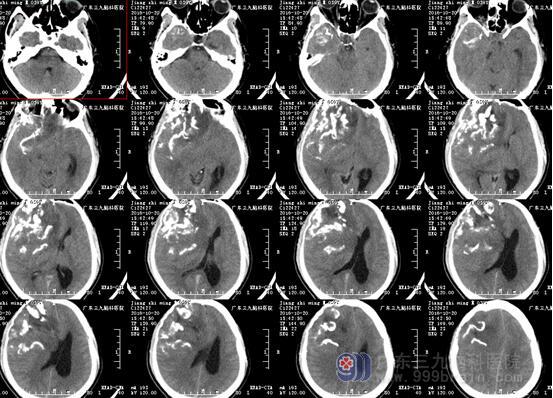

图1:术前CT显示大片状、点状钙化高密度影

少突胶质细胞瘤无包膜,与周围脑组织界限清晰,50%-80%病例出现钙化,可散在或融合成较大的钙化小体,弯曲条带状钙化为其特征性表现,但广泛钙化罕见。本例肿瘤巨大(范围约为10.8×8.6×8.7cm),CT示斑片状低密度影及条带状典型高密度钙化影,病灶内及边缘示多发迂曲血管影沿钙化斑块走行,强化后呈轻度不均匀异常强化影,均符合少突胶质瘤典型影像学改变。